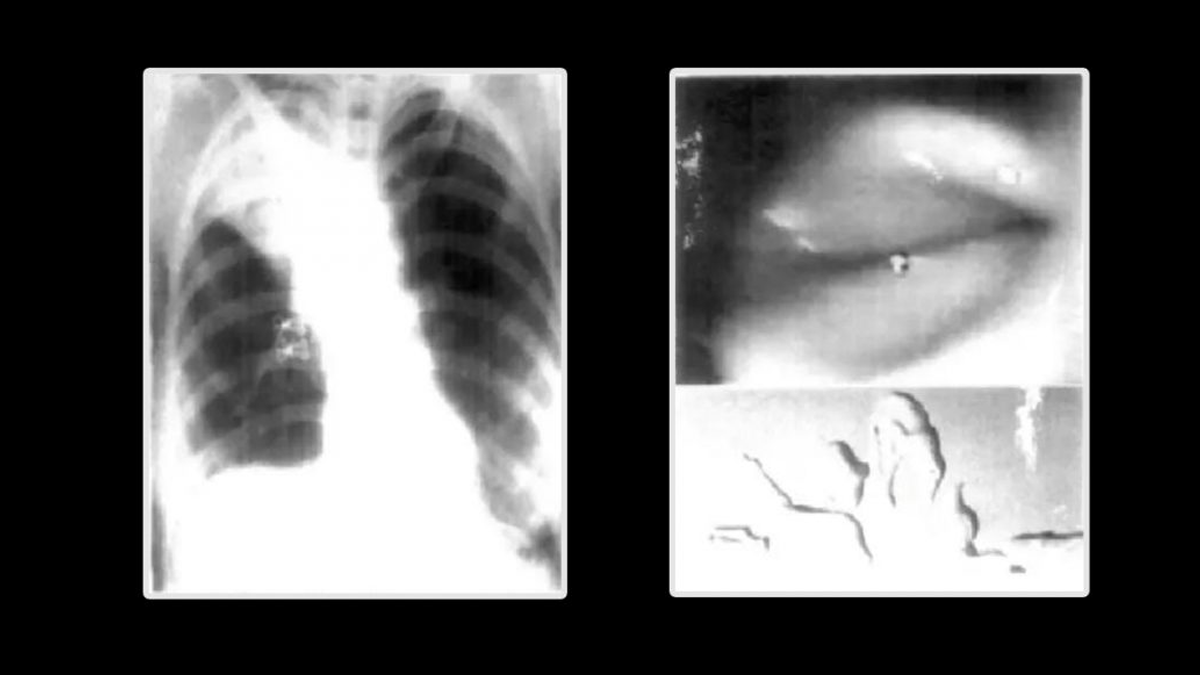

Pero al tomar una radiografía de tórax encontraron una lesión en su pulmón, tenía un colapso-consolidación no homogéneo en el lóbulo superior derecho.

Debido a la lesión que identificaron en su pulmón, los médicos decidieron realizar una videobroncoscopia en la que identificaron un objeto blanco membranoso protruyendo del bronquio en el lóbulo superior derecho colapsado.

El equipo médico procedió a realizar una broncoscopia con pinzas para extraer la misteriosa bolsa y descubrieron que era un condón, sin embargo se rompió en varias piezas por lo que le efectuaron un lavado bronquial.